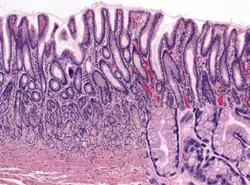

Gastric glands are glands in the lining of the stomach that play an essential role in the process of digestion. Their secretions make up the digestive gastric juice. The gastric glands open into gastric pits in the mucosa. The gastric mucosa is covered in surface mucous cells that produce the mucus necessary to protect the stomach's epithelial lining from gastric acid secreted by parietal cells in the glands, and from pepsin, a secreted digestive enzyme. Surface mucous cells follow the indentations and partly line the gastric pits. Other mucus secreting cells are found in the necks of the glands. These are mucous neck cells that produce a different kind of mucus.

The fundic glands (or oxyntic glands), are found in the fundus and body of the stomach. They are simple almost straight tubes, two or more of which open into a single duct. Oxyntic means acid-secreting and they secrete hydrochloric acid (HCl) and intrinsic factor.[7]

Types of cell

There are millions of gastric pits (also known as foveolae) in the gastric mucosa and their necessary narrowness determines the tubular form of the gastric gland. More than one tube allows for the accommodation of more than one cell type. The form of each gastric gland is similar; they are all described as having a neck region that is closest to the pit entrance, and basal regions on the lower parts of the tubes.[9] The epithelium from the gastric mucosa travels into the pit and at the neck the epithelial cells change to short columnar granular cells. These cells almost fill the tube and the remaining lumen is continued as a very fine channel.

Gastric acid regulation Human pyloric glands (at pylorus)

Human pyloric glands (at pylorus)